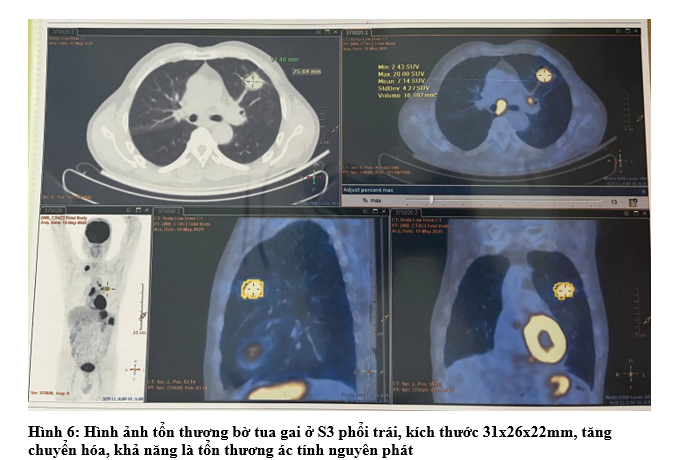

- Chụp Cắt Lớp Vi Tính Ngực: Phổi trái: thùy trên có khối ~ 27x30mm, bờ tua gai.Phổi phải: đỉnh phổi thùy trên có nốt đặc ~ 10mm.Tuyến thượng thận trái có khối ~ 21x32mm.Trung thất vị trí ngã ba khí phế quản và cửa sổ chủ phổi có vài hạch, hạch lớn nhất kích thước 10x13mm

- Chụp PET/CT: Hình ảnh dày thành đại tràng góc lách, dày nhất 18mm, trên đoạn 41mm, tăng chuyển hóa, thâm nhiễm mỡ xung quanh. Vài hạch ở cạnh tổn thương đại tràng, cạnh động mạch chủ bụng và cạnh thân tụy tăng chuyển hóa, khả năng do di căn. Hình ảnh tổn thương bờ tua gai ở S3 phổi trái, kích thước 31x26x22mm, tăng chuyển hóa, khả năng là tổn thương ác tính nguyên phát. Hình ảnh vài hạch trung thất nhóm 5, 6, 7, hạch thượng đòn Phải tăng chuyển hóa, khả năng do di căn. Hình ảnh vài nốt bán đặc và kính mờ rải rác nhu mô phổi 2 bên, có nốt tăng chuyển hóa, khả năng do di căn